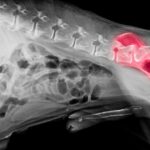

Osteoarthritis in Horses and Dogs: Understanding the Condition and Supporting Long-Term Wellness May is Arthritis Awareness Month, a time to shed light on one of the most common, and often misunderstood, degenerative conditions affecting animals: osteoarthritis (OA). Whether it’s an aging Labrador struggling to get up or a sport horse becoming subtly uneven under saddle, […]

In recognition of May as Arthritis Prevention Month, Dr. Mario Soriano, DVM and Director of Veterinary Studies at the London College of Animal Osteopathy, explains how incorporating Equine Osteopathy into the maintenance program of sport horses reduces joint injuries, increases recovery rates, and improves the overall well-being of horses. Valencia, May 5, 2025 — Joint health […]

An Overview of Common Canine Pathologies: Clinical Features, Treatment Approaches, and the Role of Osteopathy Here, we explore prevalent canine pathologies, highlighting clinical signs, conventional treatment modalities, and the potential role of osteopathy in canine care. Emphasis is placed on the scope and limitations of osteopathic intervention within evidence-based veterinary frameworks. Osteoarthritis (Degenerative Joint Disease) […]